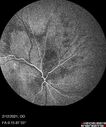

Branch Retinal Vein Occlusion with Venous Macroaneurysm (collateral)280 views66 year old female Did not notice vision loss in the right eye. The right eye has been a little worse than the left but now is much worse. Picked up during annual eye examination. VA had been 20/20 in 5 years ago.

History of brain and spinal cord radiation 1986 for T-cell lymphoma. Now with breast cancer, ablation for tachycardia, HTN

VA OD 6/200, OS 20/32Oct 16, 2021